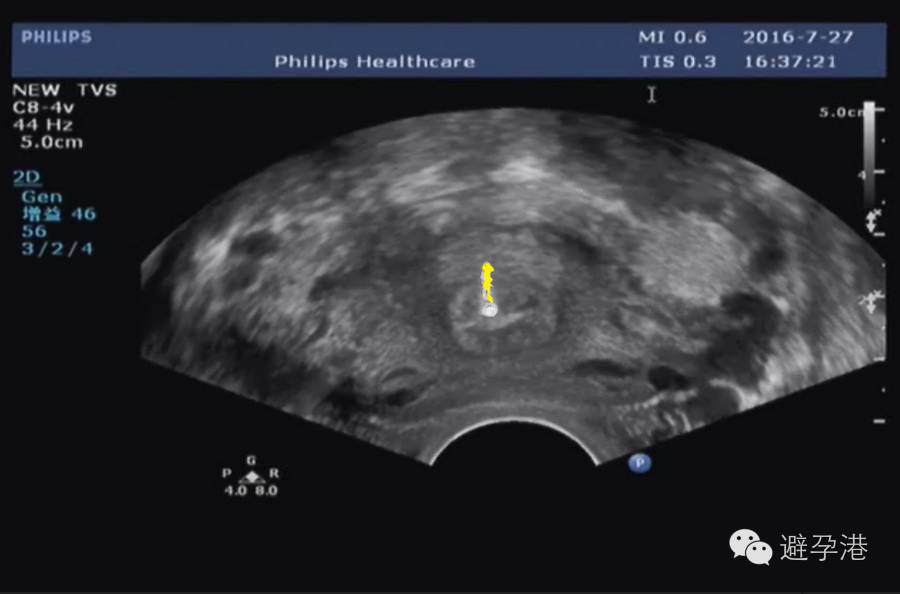

2.分辨率高超声仪器,在子宫肌壁间可见一稍强光点,为吉妮致美线结。

吉妮致美环怎么样吉妮致美节育器超声图像解读_https://www.jmylbn.com_新闻资讯_第4张

吉妮致美环怎么样吉妮致美节育器超声图像解读_https://www.jmylbn.com_新闻资讯_第5张